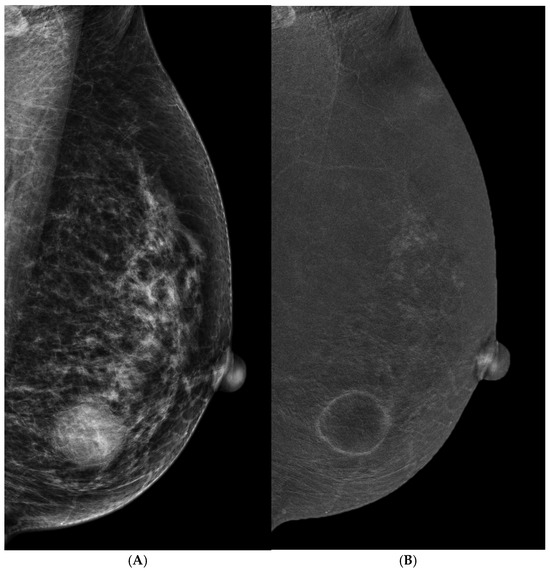

3.3. Suspicious Microcalcifications

3.4. Architectural Distortion